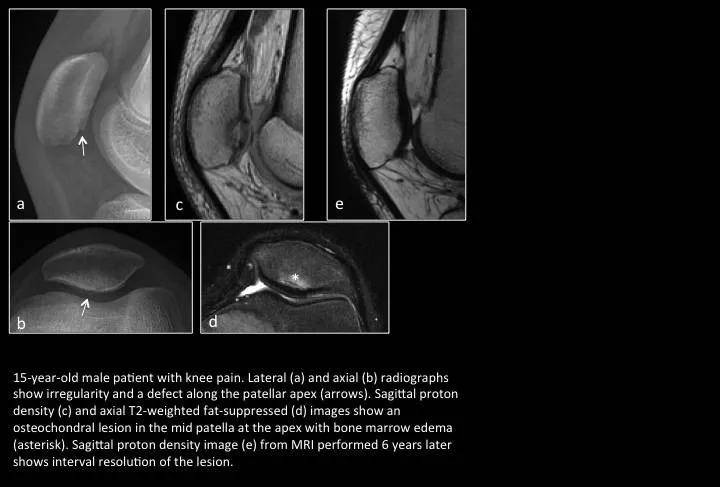

Fig. 13:Osteochondritis dissecans

图13:剥脱性骨软骨炎

15岁男孩,膝关节痛。a,b图示髌骨下级不规则 缺损;c,d图示局部骨软骨游离伴软骨下骨髓水肿;e图示6年后复查,病灶修复。